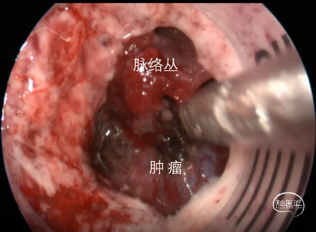

【暴露肿瘤】

【观察肿瘤】

【切除肿瘤】

【切除后观察】

本例脑膜瘤患者,经机器人辅助神经内镜下,完成侧脑室肿瘤全切除,实现了脑膜瘤精准微创治疗,同时也对神经功能起到良好的保护。

应用神经内镜的优势有:1、切口小/无切口:切口小,直切口和小骨窗即可进行手术或者经鼻腔、口腔无表面切口。2、正常组织损伤小:大脑皮层损伤小,手术通道相对固定,对周围脑组织牵拉更小,同时有效限制手术器械移动造成的脑组织损伤。3、视野更好:神经内镜更好的照明,视角开阔且显露清晰,神经内镜可提供近距离及多角度的视野观察,更有助于辨别肿瘤与周边解剖结构的关系,提高全切率,并有效避免神经损伤。切除脑膜瘤时病变定位也是关键的问题,特别是深部肿瘤,定位尤为重要。